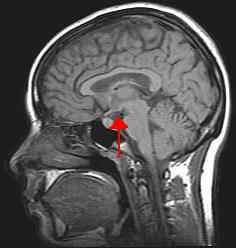

Hypothalamus

What is this entire structure?

Pituitary Gland (AKA Hypophysis)

What is #4 and what hormones does it secrete?

Anterior Pituitary (AKA Adenohypophysis)

What is #6 and what hormones does it secrete?

Posterior Pituitary (AKA Neurohypophysis)

What is the fancy latin name for #4?

pars distalis

What’s the fancy latin name for #6?

pars nervosa